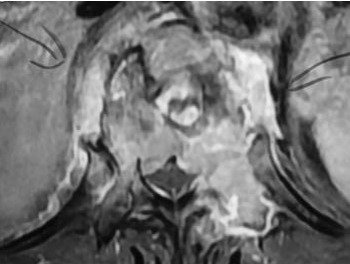

Madam B, a 72-year-old female, presented to my clinic recently with 3 months history of low back pain radiating to her left supra-iliac region. Her symptoms had worsened progressively. She had tenderness elicited by lumbar spine flexion. Neurological examination of her lower limbs was normal. X-ray and MRI of her spine revealed an extensive infiltrative lesion of T11 vertebral body, and its left pedicle. The posterior wall of the vertebra was eroded, and the lesion was encroaching onto the spinal cord and compressing it. The assessment was an extensive T11 spinal metastasis with cord compression and high risk of pathological fracture that could result in paralysis. Madam B underwent T11 decompression laminectomy with clearance of tumor tissue immediately surrounding the cord. The spine was instrumented from T8 to L1 segments to provide stability and to pre-empt pathological fracture. Frozen section of the specimen taken during surgery indicated the lesion to be lymphoma. This was later sub-typed as diffuse large B-cell lymphoma. Her back pain resolved completely following the surgery and she was ambulating well. She was referred to hematologist for outpatient chemotherapy treatment which started one week following the surgery.